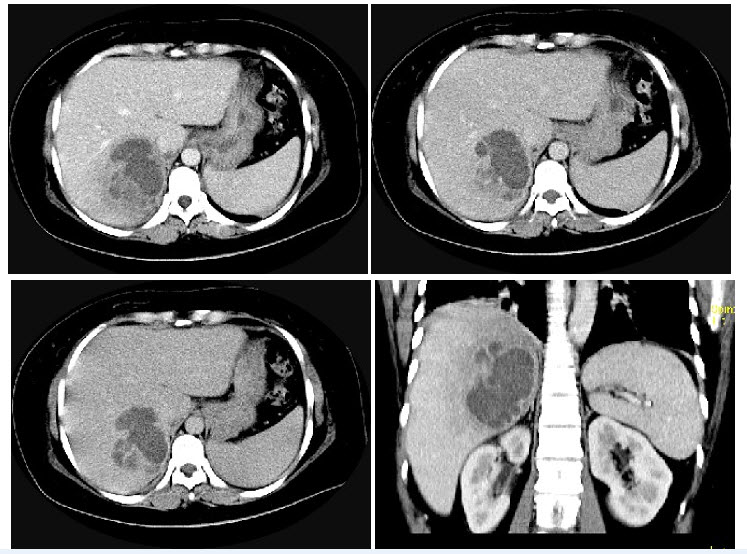

C.观察纵隔淋巴结肿大

男,60岁,曾患乙肝、肝硬化多年,右上腹胀痛1月余,AFP为80.8μg/L,CT检查如图所示,最可能的诊断是()